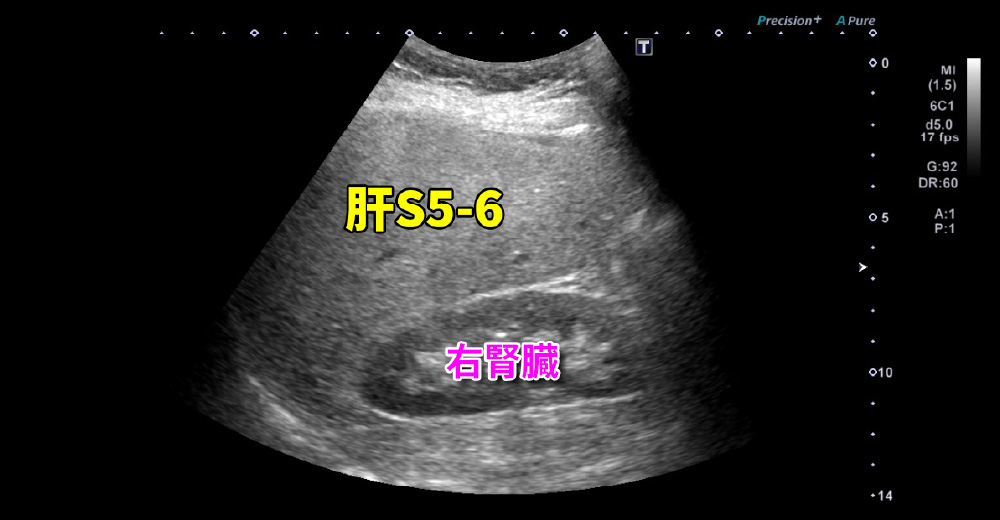

腹部エコー所見

“肝臓”が“腎臓”より明るい ~ 肝腎コントラスト陽性